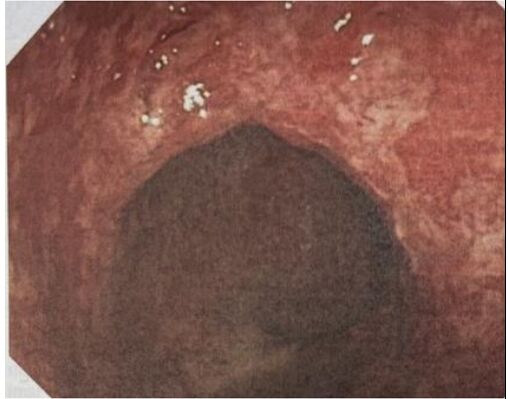

54. 25歲男性,因反覆性血便,每天3-4次,合併腹痛、裏急後重(tenesmus)等症狀,接受全大腸鏡檢查,結 果如圖,血液ESR: 20mm/h,下列敘述,何者錯誤?(1)疾病嚴重度為moderate (2)血 液anti-saccharomyces cerevisiae Ab常為陽性 (3)眼睛有可能發生uveitis (4)抗生素治療有不錯效果 (5)NOD2基因與此病發生有關

(A) (1)+(2)+(3)。 (B) (2)+(3)+(4)。 (C) (3)+(4)+(5)。 (D) (2)+(4)+(5)。 (E) (1)+(4)+(5)。